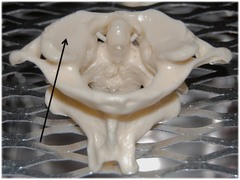

Atlas

Name the entire bone indicated by the arrow.

96

New cards

Axis

Name the entire bone indicated by the arrow.